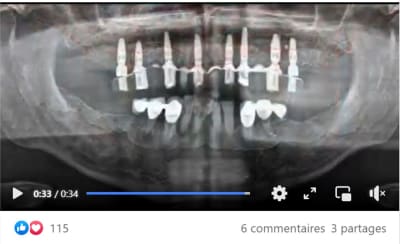

Un exemple d'un cas plébiscité pourtant lacunaire

j'y vois des greffes de sinus en vu d'une MCI se qui implique environ 6 mois d'attente avec un antago précaire.

30/06/2022 à 09h06

la conservation des dents résiduelles pour positionner le guide conduit à une répartition non équilibrée des implants

30/06/2022 à 19h20

Ce qui est prévu 9 implants

résultat, seul 6 implants mis en charge

Pour conclure avec ce cas qui n'a suscité aucun commentaire, voici celui qui accompagnait

la vidéo d'où sont extraites les photos : "Affaire du jour. Une partie du cours de protho commence dans 2 semaines. Apprenez à simplifier les cas d'implant en arche complète de façon prévisible.

Concept star inspiré par..."

Son auteur propose une formation de simplification en réhabilitation totale de maxillaire en prothèse implanto-portée e présentant un cas qui démarre avec 11% d'échec implantaire.